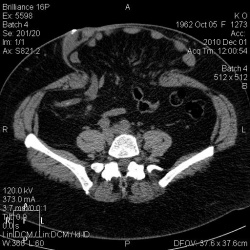

Женщина 1962 г.р. В анамнезе псевдокиста поджелудочной железы, прооперирована около 6 мес назад. Фистуло-КТ. И красавица грыжа. Реконструкции: